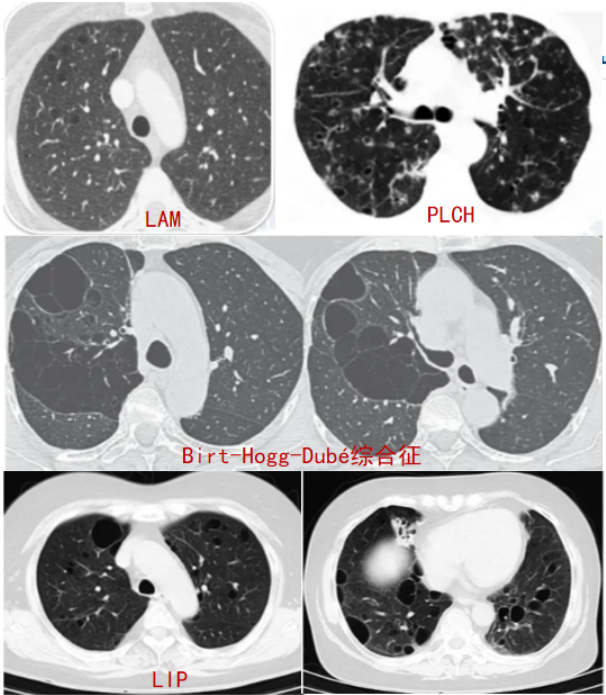

患者影像学改变主要为双肺弥漫性气囊样病变,此种改变类似于淋巴管平滑肌瘤病(LAM)、肺朗格汉斯细胞组织细胞增多症(PLCH)、淋巴细胞性间质性肺炎(LIP)。对于LAM而言,患者主要以育龄期女性为主,影像学主要表现为两肺多发小结节以及小叶间隔增厚,并且伴有多发磨玻璃影。

本例患者并无典型的LAM影像学特征。尽管PLCH也会出现弥漫性气囊样病变,但其往往伴有多发小结节,且两上肺多见,肋膈角相对正常。此外,肺囊肿Birt-Hogg-Dubé综合征和神经纤维瘤病通常也会出现肺部多发气囊样病变,但其影像学往往呈单侧多发囊性灶,形态大小不一,且以胸膜下改变为主,多发分隔薄壁囊性灶。LIP患者的气囊样病变为多发薄壁囊性灶,散在分布于肺内和支气管血管束周围。这与我们之前救治的一例干燥综合征患者类似。经过影像学分析讨论,考虑该患者的影像学表现更倾向于LIP改变。

图片

注:几种疾病弥漫肺气囊样病变的表现。LAM为淋巴管平滑肌瘤病,PLCH为肺朗格汉斯细胞组织细胞增多症,LIP为淋巴细胞性间质性肺炎。